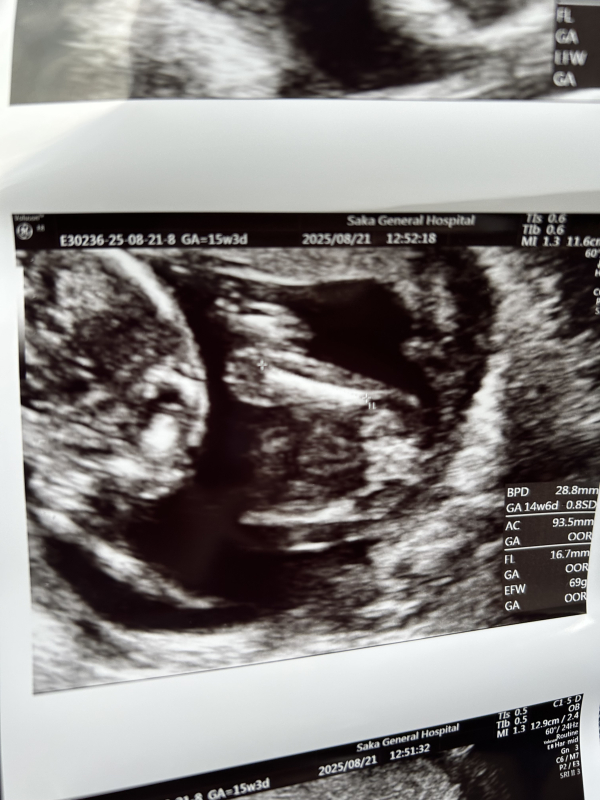

あかちゃんの顔

超音波写真についてのご相談ですね。

お写真もありがとうございます。

赤ちゃんの頭上から撮っている感じなのかなと思います。

私からみて、特に異常な感じには見えないのですが、骨が白く映るので、角度の関係で赤ちゃんの可愛いイメージとは違う印象なのかもしれません。

超音波写真について気になることがありましたら、健診時に医師へ聞いていただくのが良いかなと思います。